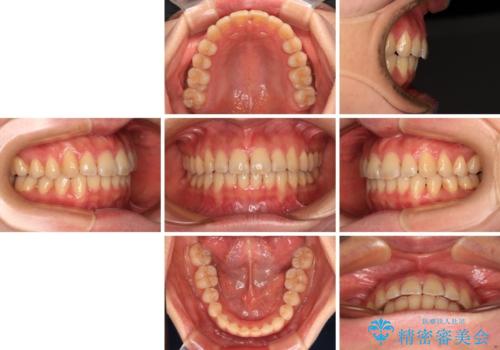

僅か1年間できれいに歯列を整えることができ、患者様には大変満足していただきました。